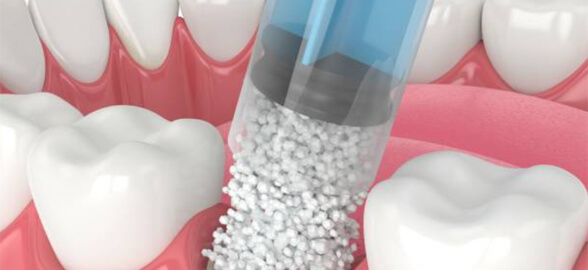

La régénération osseuse en dentisterie est essentielle pour toute une série de traitements, de la pose d'implants dentaires à la restauration de défauts osseux causés par des malad